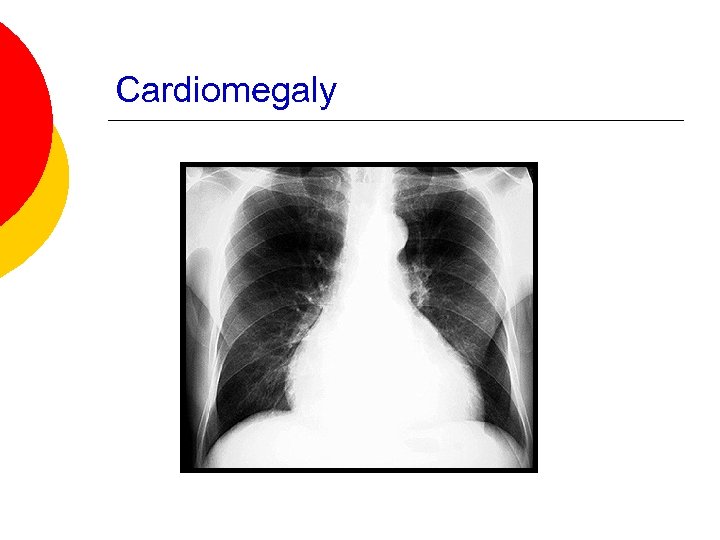

Chest X-ray in Heart Failure Cardiomegaly ¡ Cephalization of the pulmonary vessels ¡ Kerley B-lines ¡ Pleural effusions ¡

Cardiomegaly